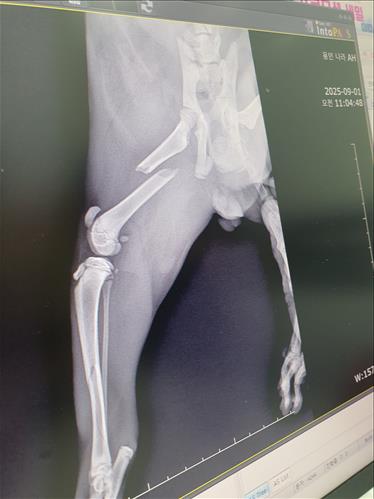

지게차로 다리를 눌러서 오른쪽 뒷다리를 사용하지 못하고 있습니다. 깁스만 할정도면 치료를 진행하려고 했으나 상태가 심각하여 수술을 해야한다고 합니다. 수술비용이 부담스럽지만 100만원선이면 수술해주고 싶습니다.

첨부해주신 엑스레이 사진을 보면 오른쪽 뒷다리 대퇴골 골절이 심하게 어긋나 있고, 골반 쪽까지 손상이 동반됐을 가능성이 있습니다. 단순 깁스만으로 치료는 어렵고 수술을 해야하는 상황이 맞습니다.

수술 비용은 마이펫플러스에 등록된 다리 골절 상품에서 [후지 골절] 중 대퇴골 골절 금액을 참고해보시면 도움이 될 것입니다. 다만, 골반 손상 동반 여부에 따라 난이도와 비용에 차이가 발생할 수 있겠습니다.

수술 후에는 최소 4~6주 절대 안정이 필요하고, 회복 상태에 따라 약물 치료와 재활 치료를 병행할 수 있습니다. 수술 후에 약간의 절뚝임이나 관절 강직이 남을 수도 있는 점도 고려해야합니다.